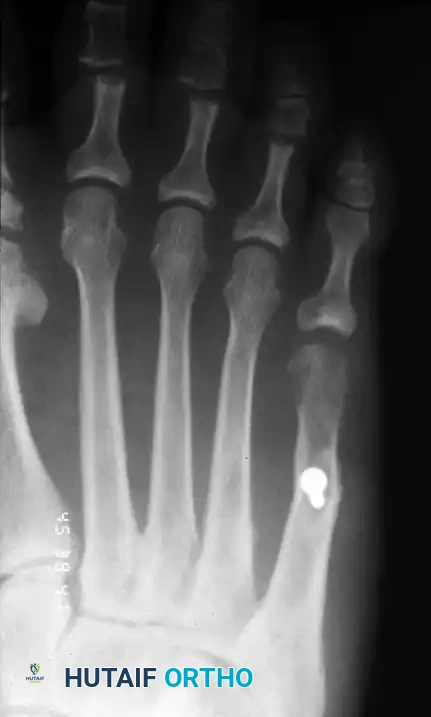

Classification of Bunionette Deformity

The classification system proposed by Cohen and Nicholson is the most widely accepted framework for categorizing bunionette deformities. It is based entirely on the structural radiographic appearance of the fifth metatarsal and directly guides surgical intervention.

Type I: Enlarged Metatarsal Head

Type I is characterized by an isolated enlargement or lateral prominence of the fifth metatarsal head. The 4-5 IMA and the lateral deviation angle remain within normal limits. This is often described as a "dumbbell-shaped" metatarsal head.

FIGURE 83-41A Type I, lateral prominence of the metatarsal head.

Type II: Lateral Bowing of the Metatarsal Shaft

Type II features an abnormal lateral bend or bowing of the distal third of the fifth metatarsal shaft. The 4-5 IMA is normal, but the Lateral Deviation Angle (LDA) is significantly increased.

FIGURE 83-41B Type II, lateral bowing of the fifth metatarsal.

Type III: Widened 4-5 Intermetatarsal Angle

Type III is the most common variant. It is characterized by a divergent fifth metatarsal shaft resulting in an increased 4-5 IMA (greater than 8 degrees). This divergence significantly widens the forefoot (splayfoot).

FIGURE 83-41C Type III, widening of the 4-5 intermetatarsal angle.